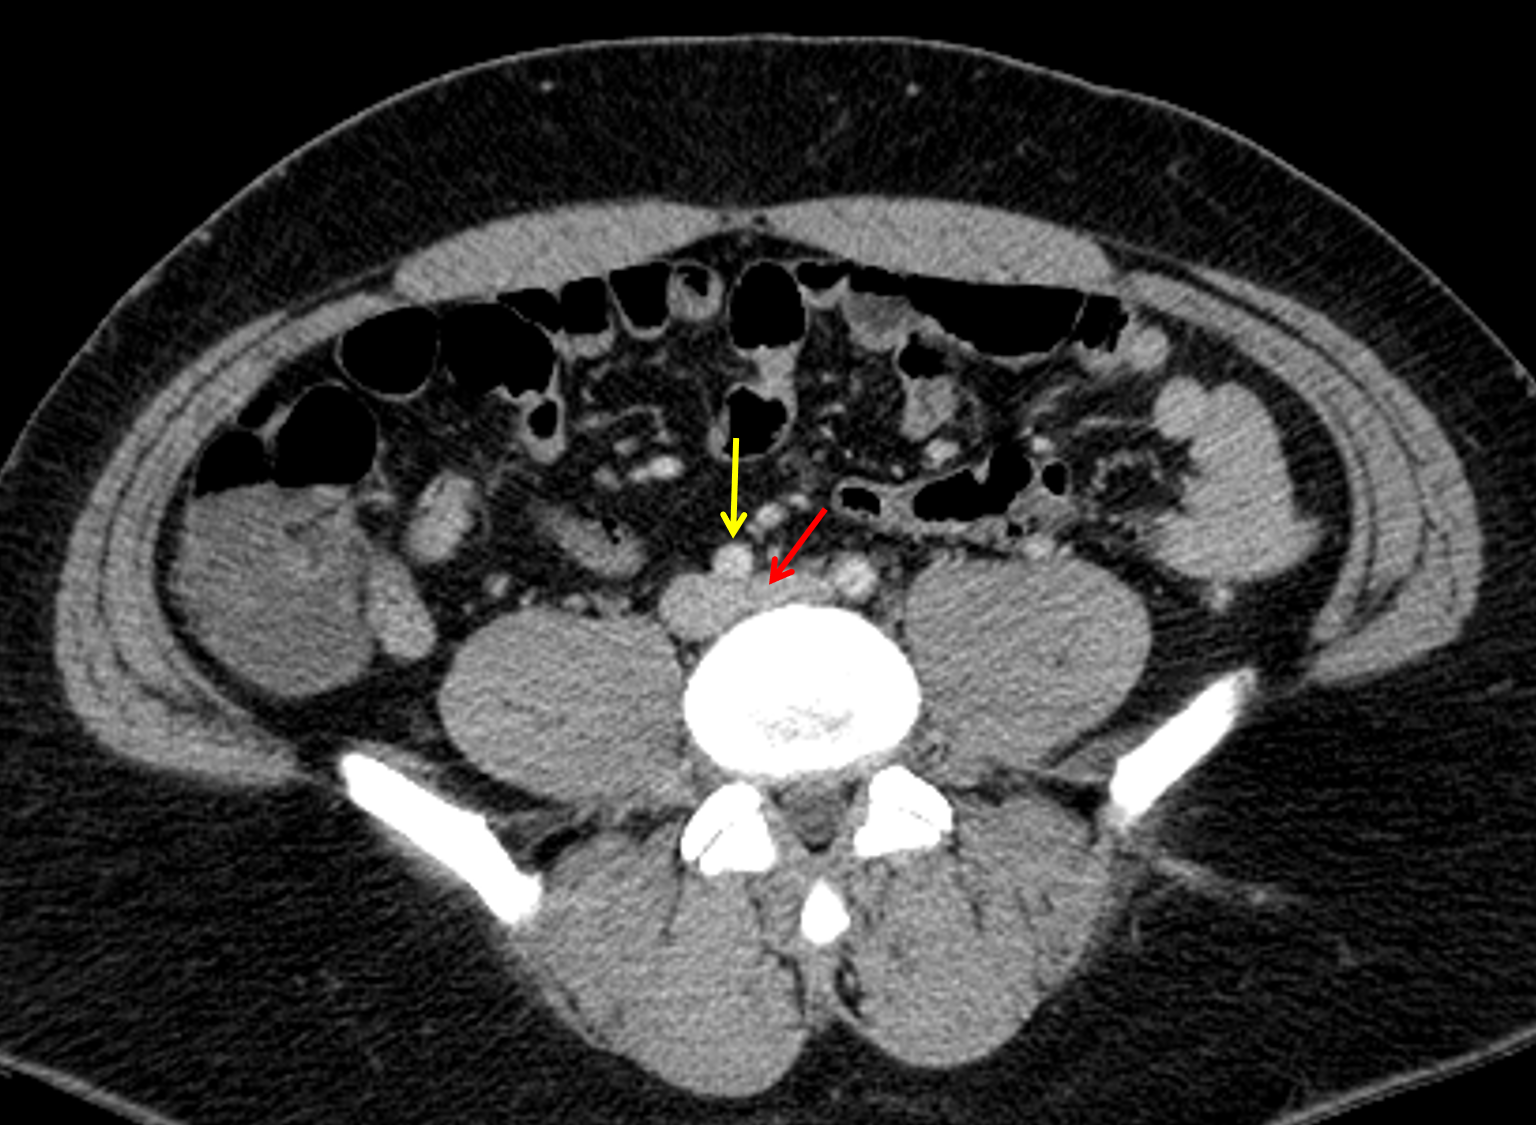

Age: 32

Sex: Male

Indication: Left leg swelling

Sample ReportOcclusive deep venous thrombosis of the left common and profunda femoral veins extending proximally into the left external and common iliac veins, incompletely assessed on this study. This configuration is suggestive of May-Thurner syndrome and can be further assessed with contrast-enhanced CT of the abdomen and pelvis.